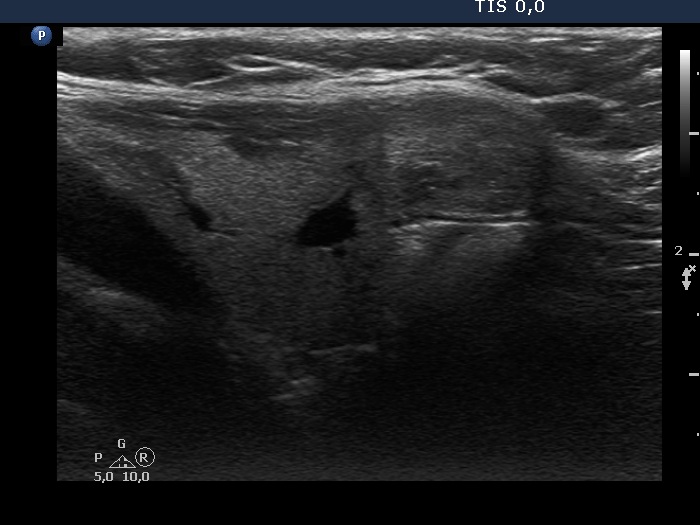

Ultrasonography. The thyroid was echonormal. There was a moderately hypoechoic nodule in the isthmus. The nodule had several intranodular hyperechogenic figures, probably back wall figures. The nodule did not show increase in size over the part two decades.